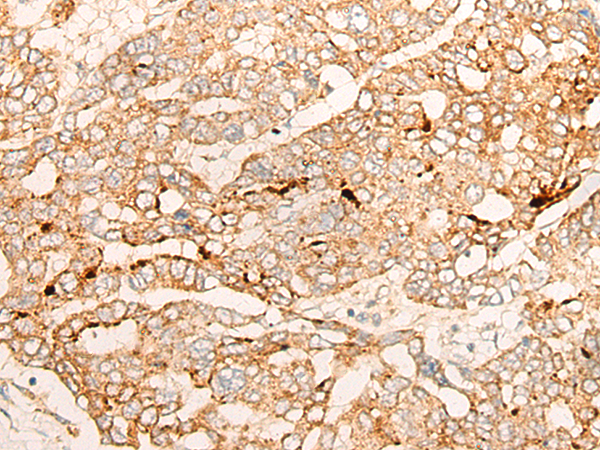

IHC positive control: |

Human liver cancer and Human esophagus cancer |